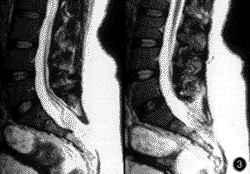

查体 发育营养中等,全身一般情况尚可。骶尾部稍偏左可见8cm×6cm的包块,表面皮肤颜色正常,质软,边界不清,移动差,触压时肛门、会阴部有疼痛、麻木感;肛周皮肤感觉迟钝;尾骨处有轻压痛,触摸时似有脱位;肛门括约肌收缩力弱,下肢感觉、运动正常;膝及跟腱反射正常,直腿抬高试验(-)。血、尿、便及肝功能常规实验室检查正常。腰骶部X线摄片显示骶椎隐性脊柱裂,骶尾交界处半脱位,远端向后脱位(图1,2)。MRI显示腰骶部脂肪瘤,脊髓低位,位于L4椎体下部,脂肪瘤经脊柱裂侵入椎管与终丝粘连形成栓系(图3,4)。

图3 脂肪瘤经脊柱裂侵入椎管(MRI)

图4 脂肪瘤经脊柱裂侵入椎管